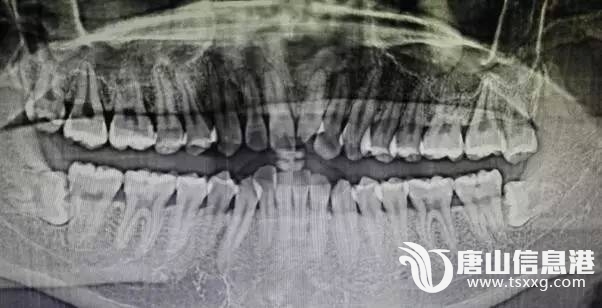

(张某受伤的部位)华北理工大学学生张某在阳光100健身连锁健身期间,因健身房跑步机调试致张某摔倒,并导致一颗门牙断裂,一颗门牙隐裂,嘴唇撕裂,身体多处摔伤,后健身房无人处理,张某自行去医院治疗。3月15日

d9715c1863789871fac9c8ae473b346f.jpg

(张某医院诊断结果)张某从健身房要到保险公司电话,通过跟保险公司沟通,保险公司回话:①保险公司与健身房保险合同上已写明牙齿属于整容范畴,不在保险范围内;②被保人是健身房,与张某无关,需张某自行与健身房协商理赔事宜。6月20日张某与健身房总经理阮某电话沟通,并将保险公司告知阮某后,在与其协商期间,阮某辱骂张某,后张某等人去健身房与阮某理论,阮某扬言要找社会上人弄张某。